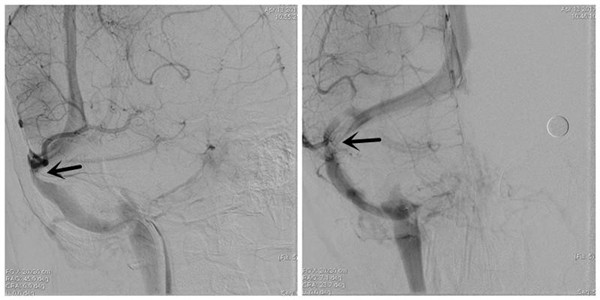

经过充分的术前准备,脑脊液鼻漏停止、颅内感染完全控制后。于4月13日在全麻下为患者行右侧横窦、乙状窦狭窄支架成形术。手术由牛晓丽主治医师麻醉,崔刚、许刚副教授手术,张尚军技师、刘敏龙主治医师及屈满丽护士配合,杨庆余教授指导。首先对患者狭窄静脉窦远、近端压力差进行了测定,远近端压力差210mmH2O,然后对狭窄部位进行了球囊扩张,最后释放支架。手术过程顺利,支架释放后狭窄远、近端压力差降为零。术后即刻患者诉头痛、头胀感觉立即消失,停止使用脱水药后患者头部也无不适,3天后腰穿压力正常,已于近日出院。出院时患者及家属激动地说“你们不仅治好了我的病,而且断清了我们家庭内部2年的官司!”最后,患者丈夫补充了句:我再也不用“背黑锅”了!

术前DSA示:右侧横窦狭窄(箭头所示)